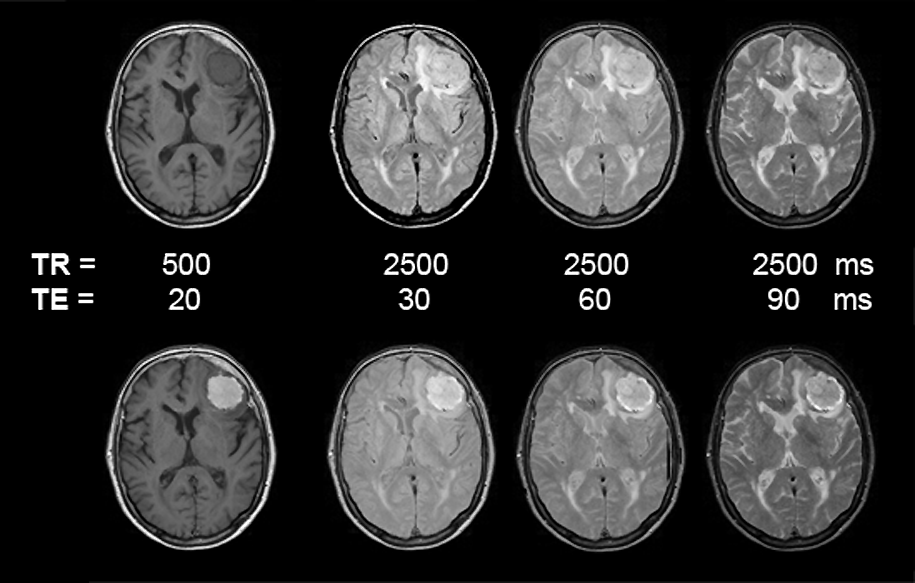

Figuras 13-09:

Pa­tient with a meningioma. Multiple SE sequence before (top row) and after (bottom row) intravenous application of a gadolinium contrast agent. The images to the left are heavily T1-weighted, then ρ-weighted, and to the right increasingly T2-weighted.

Simulation software: MR Image Expert®

The patient of the figure above has a huge meningioma in the left frontal lobe. It is easily visible on the non-enhanced images, mostly because of its mass effect and the bright surrounding edema on T2-weighted images. Yet, this case is a good example of the enhancement pattern of gadolinium contrast agents. This kind of tumor enhances brightly on T1-weighted images; there is still enhancement on ρ-weighted images. T2-weighted images, however, show the same contrast pattern before and after injection of the agent. If the meningioma or similar enhancing lesions are very small and no indirect signs of lesions can be found, only contrast enhancement will reveal the pathology (see also Figure 13-04 and Figure 13-08).